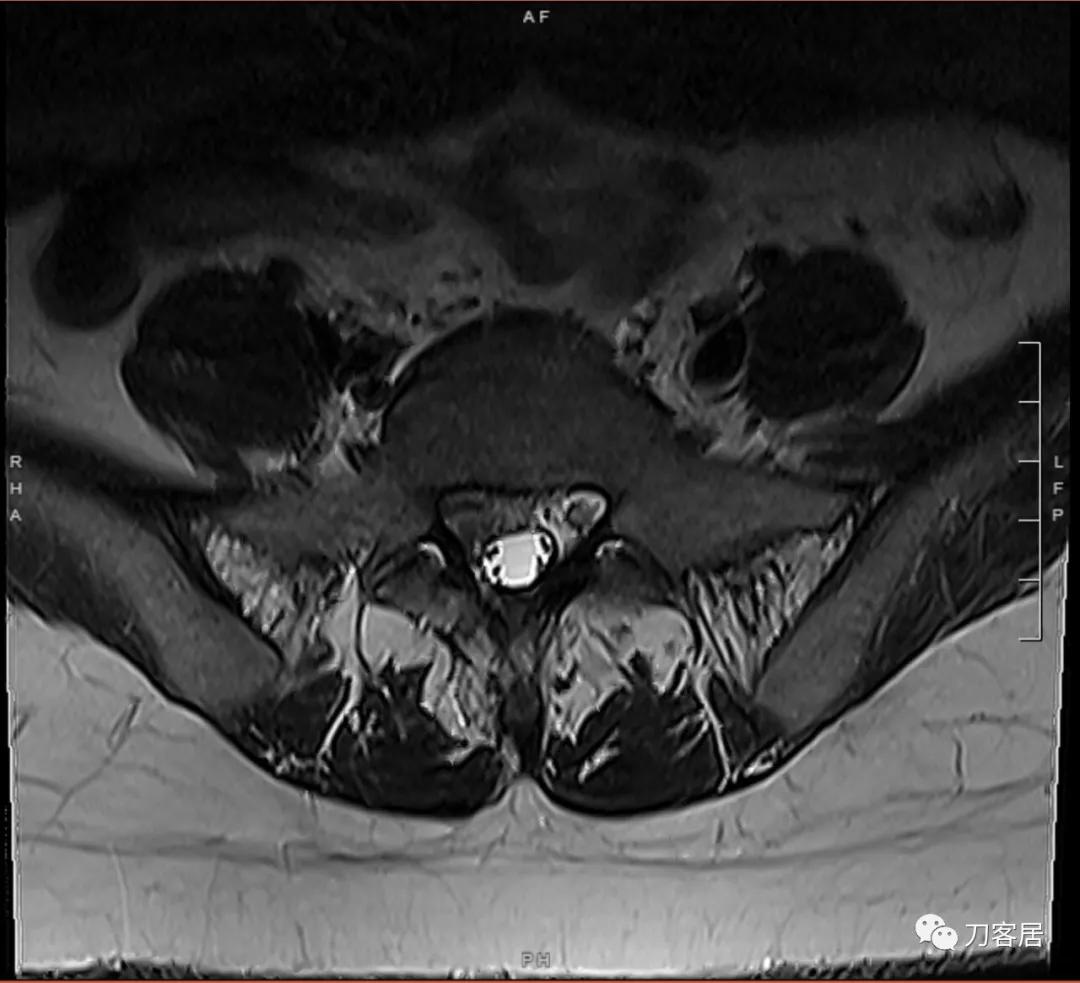

以下是患者的影像资料:

图4. 微创术前腰椎MRI横截面,提示腰5骶1椎间盘突出,右旁侧型。